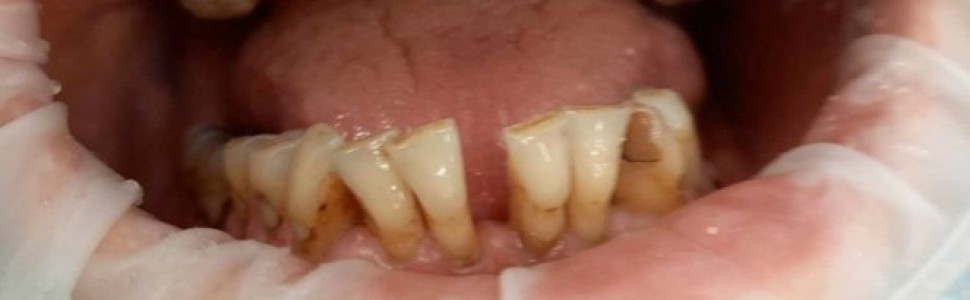

Do mojego gabinetu zgłosił się pacjent, lat 51, zaniepokojony zwiększoną ruchomością dolnych zębów siecznych (ryc. 1). Kilka miesięcy wcześniej stomatolog poinformował pacjenta, iż ruchomość jest związana z chorobą przyzębia i zastosował unieruchomienie zębów drucianą ligaturą. Jednakże szyna nie była stabilna, utrudniała pacjentowi mówienie oraz drażniła język i błonę śluzową dolnej wargi, dodatkowo pacjent nie zaakceptował szyny ze względów estetycznych. Ostatecznie szyna została usunięta. Czy są inne możliwości unieruchomienia zębów u pacjenta?

Ryc. 1. Zdjęcie uzębienia pacjenta z ruchomością zębów siecznych żuchwy.